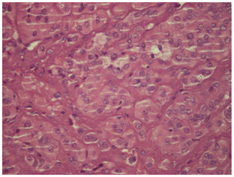

Pathological examination of the tissue sections revealed a 1,5 cm circumscribed neoplasm with tan color partially encapsulated, covered by healthy parotid tissue. A lymphe node 2,1 cm was also present but had non specific reactive changes. The neoplasm had a nested pattern of growth suggesting an oncocytoma. It composed of cells with vesicular nuclei, with prominent nucleoli and abundant granular acidophilic cytoplasm. (Figure 1) (Figure 2). Enhanced mitosis, cytological atypia, moderate nuclear pleomorphism and necrosis were noted. Focally an abnormal circumference with connective tissue and fibrous elements was also present suggesting that this neoplasm has agressive histological features with malignant potential. Immunohistological staining pattern showed that the neoplastic cells had a Ki67 positive at 8% (Figure 3), positve for ker 8/18 (Figure 4), positive-negative for p63 while were negative for ker 14, SMA, CEA, TTF-1, CD31, calcitonin, EMA, GFAP, and S100 staining.

Figure 2 HEx 40: Nested pattern of neoplasm composed of cells with vesicular nuclei and abundant granular acidophilic cytoplasm. Vesicular nuclei with prominent nucleoli.